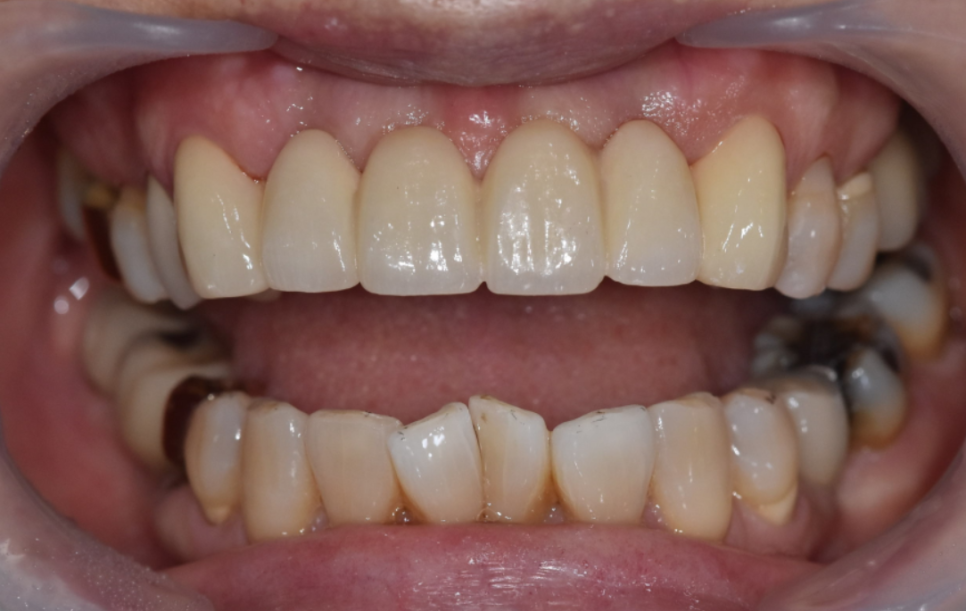

240708 임시치아

임시치아, 옆 위아래 모두 확인하여 조정

이 임시치아로 환자분과 크기나 모양에 대한 의견을 나눕니다.

기공소가 병원 안에 있으니까 환자분의 의견을 바로바로 반영 가능.

"이 모양 어떠세요? 크기는 괜찮으세요?"

"조금만 더 작게 해주실 수 있을까요?"

하나하나 반영해서 다시 만들고, 또 확인받고.

이 과정을 여러 번 반복했습니다.